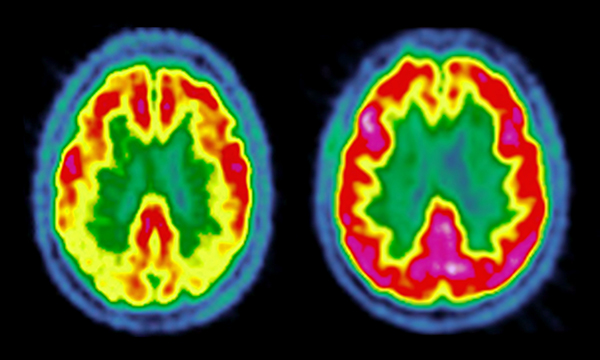

Review of Mueller C, Ballard C, Corbett A et al (2017) The prognosis of dementia with Lewy bodies. The Lancet. Neurology. 16, 5, 390-398.